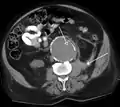

An axial contrast-enhanced CT scan demonstrating an abdominal aortic aneurysm of 4.8 by 3.8 cm